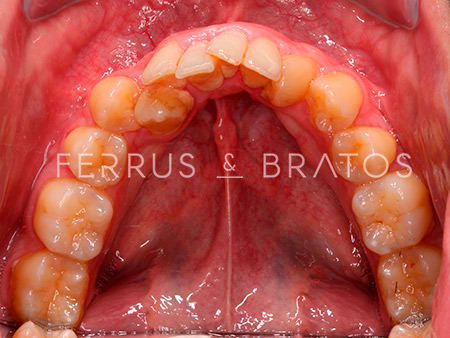

Raúl presentaba diversos problemas relacionados con su mandíbula: apiñamiento severo, una sobremordida muy aumetada y una ligera clase II dentaria. Cuando acudió a nuestra clínica, la doctora Patricia Bratos planificó un tratamiento con ortodoncia de brackets de Zafiro, un sistema muy estético y eficaz.